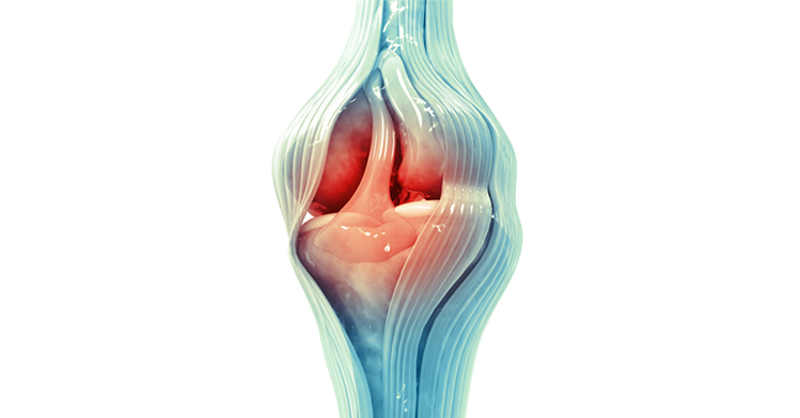

Joint point

Joint point 136 фотографий